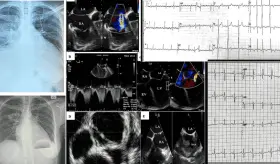

Paciente con marcapasos reciente desarrolló endocarditis infecciosa por Staphylococcus epidermidis complicada con pseudoaneurisma del intervalo mitral-aórtico y perforación valvular mitral.